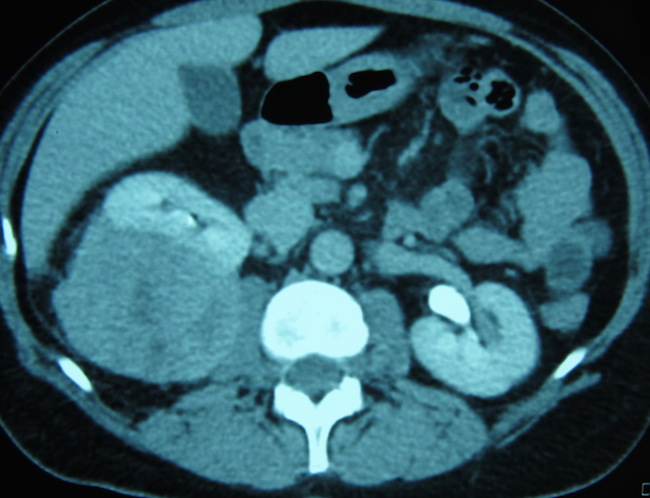

злокачественная шванома